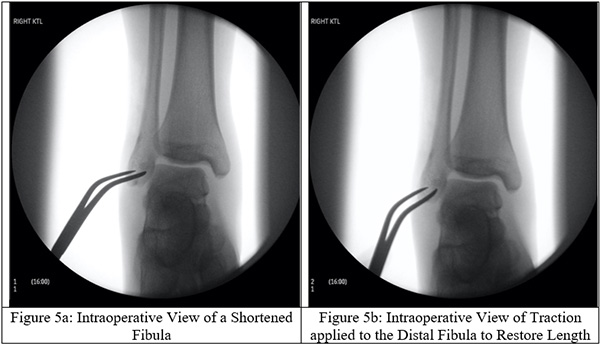

Surgical intervention is a definitive form of treatment for ankle instability and the associated fibular fracture. The proximal fibular fracture is not directly stabilized, but instead indirectly stabilized through fixating the distal fibula to the tibia with trans-syndesmotic screws (Figures 5a-f). To restore the fibular length, the distal end of the fibula is elongated into its anatomical position for trans-syndesmotic fixation. Other stabilization techniques have been described in the literature such as the use of bioabsorbable screws, syndesmotic staples, circular wire external fixators, Kirschner wires, flexible implants, syndesmotic hooks, syndesmotic bolts, and cerclage wires.[12] Metal screw fixation or a suture loop between two buttons, or some combination of the two, still stands to be the most popular choice among orthopedic surgeons. Use of screws carries the downside of requiring an additional surgery to remove the screws but may be more effective at maintaining length. By utilizing these screws, the fibular length is properly restored and the ankle mortise is appropriately reestablished. Suture loops between buttons (the ankle “tightrope”) has the advantage of not requiring screw removal but may not be as effective at maintaining fibular length.